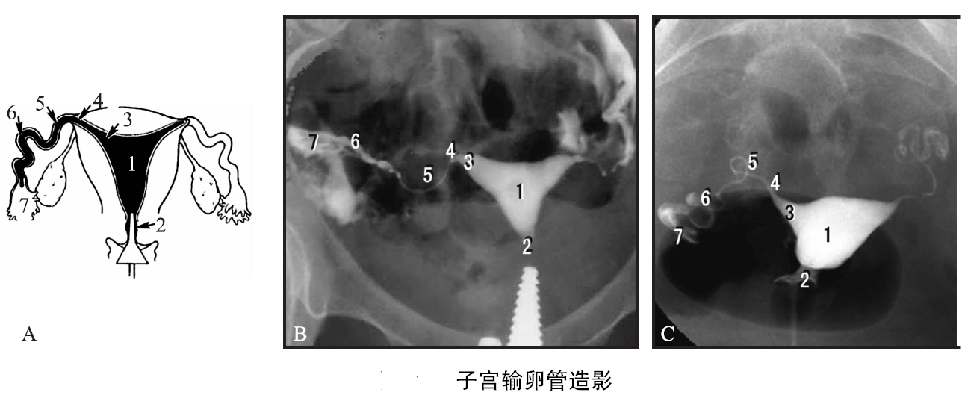

二、了解子宫和输卵管、输精管和精囊腺造影,了解盆部动脉造影。